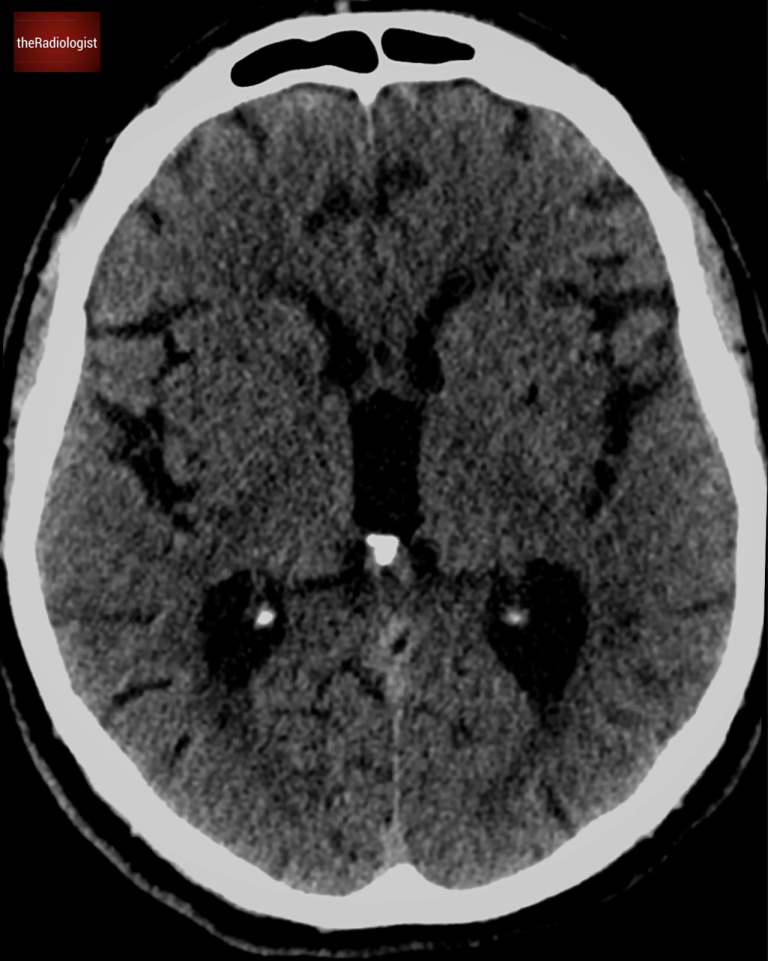

Axial slice of a non contrast brain CT at the level of the 3rd ventricle. Does it show an abnormality?

Going back to our case on the right sided image below, looking at both middle cerebral arteries, they appear equal in density, so there is no hyperdense MCA sign present.

On the left we have an example of a positive right sided hyperdense MCA in a case of acute stroke. In our case on the right sided image, the middle cerebral arteries are equal in density and considered normal.